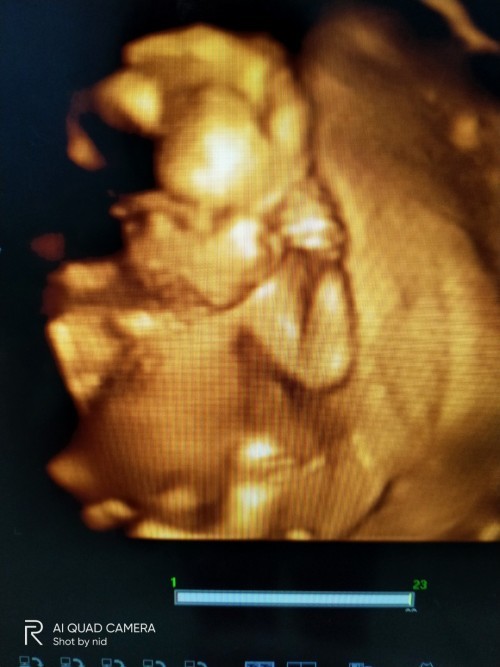

ภาพซาวด์4มิติ

ขอดูภาพซาวด์4มิติ ของแม่ๆท่านอื่นหน่อยคะ บ้านนี้ซาวด์ปัยน้องยิ้มเล่นไปด้วย ให้ทายว่าน้องเปนผญ.หรือผช.😊